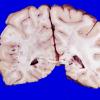

MYELIN (NON-IMMUNE MEDIATED)

Fat Embolism (9)